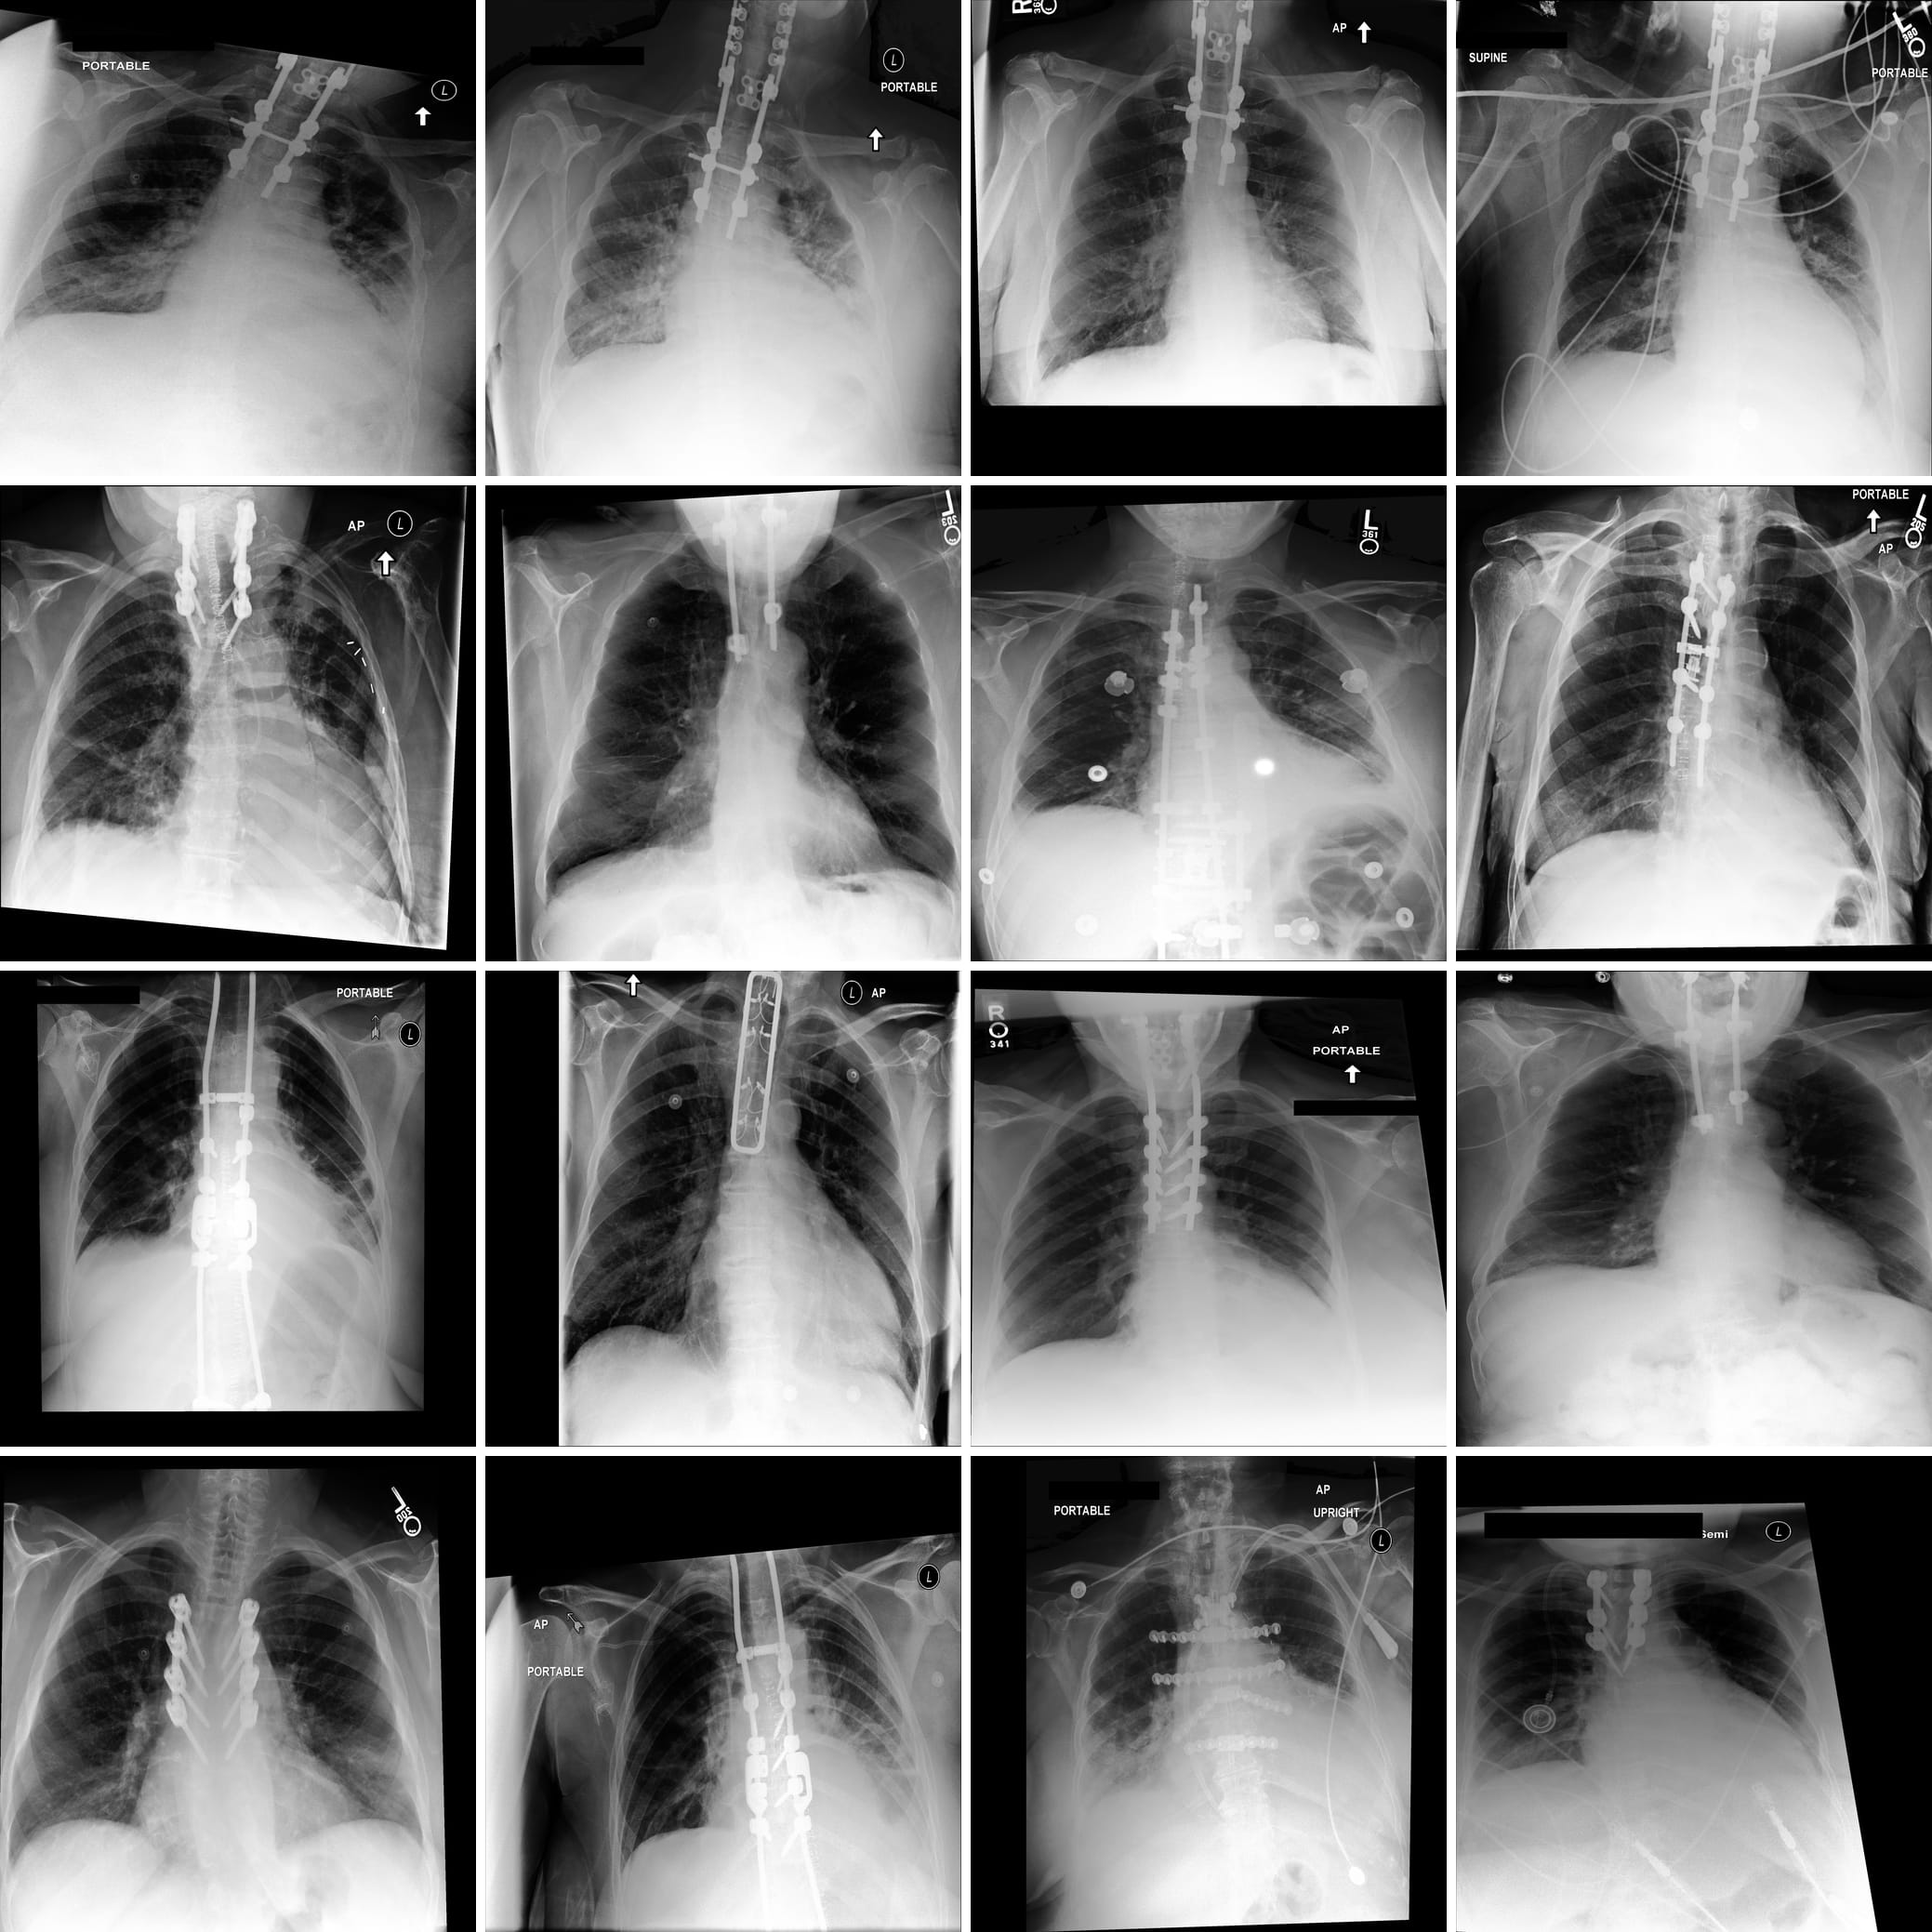

Figure 1 displays some clinically relevant SAE features. In this section we showcase highest activating images for a number of other features, as well as the corresponding feature explanations. We highlight the variety of features captured by SAE-Rad, from instrumentation features to visual features such as radiograph inversion, pathology-related features, and small details such as piercings.